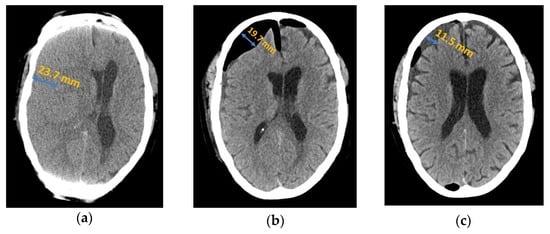

Figure 5.

Intake of anticoagulant medication in patients with and without recurrence.